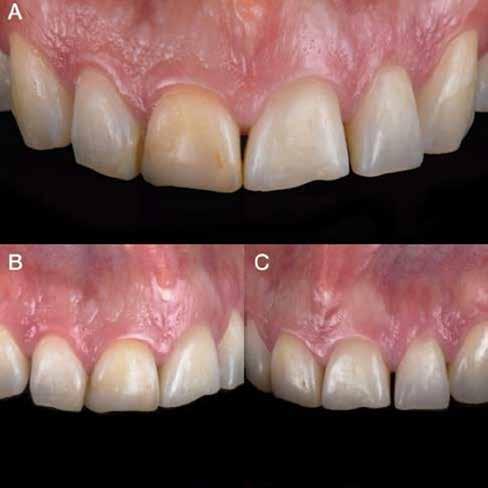

A rendelésünkön egy 34 éves latin-amerikai nőbeteg azzal a panasszal jelentkezett, hogy a fogait „túl rövidnek” találja, és ezen felül a mosolyával sem volt megelégedve. Az anamnézisfelvétel alapján egészséges volt, elmondása szerint rendszeresen járt orvoshoz. Öt évvel korábban néhány hátsó fogát restaurálták. Páciensünk szájhigiénéje megfelelő volt,

a fogait rendszeresen ápolta. House klasszifikációja szerint, amely a pácienseket a fogászati kezelésekhez való attitűdjük szerint négy csoportba sorolja, a páciensünk a szabálykövető csoportba tartozott.

Az előzetes állapotfelmérést és a kezelés megtervezését követően a fogakat minimál invazív módon preparáltuk (1. a-b ábrák), majd az előkészített fogak ínybarázdáiba fonalbehelyező eszköz segítségével (113 Serrated Gingival Cord Packer, Hu-Friedy, Chicago, Illinois) teflonszalagot helyeztünk (Loctite Thread Seal Tape, Henkel Loctite Corp., Egyesült Államok), (1. c ábra). A hagyományos retrakciós fonalak helyett, a rugalmasságuk miatt előnyösebbnek tartjuk a teflonszalagok használatát. A kofferdámot (Dental Dam, Nic Tone, Bukarest, Románia) az előkészített fogakon kívül, az azoktól disztálisan elhelyezkedő egy-egy fognak megfelelően is perforáltuk.

Az oxigén inhibíciós réteg kialakulásának elkerülése érdekében a kerámiafelszíneket glicerin géllel (Liquid Strip, Ivoclar Vivadent, Schaan, Liechtenstein) borítottuk, majd ezeket a felszíneket ismét 20-20 másodpercen keresztül világítottuk. A végeredmény megfelelt a páciens esztétikai igényeinek (6. a. ábra). Az átadott restaurátumok épségének megőrzése érdekében, a páciens számára éjszakai fogvédő sín készült. Az ötéves kontroll alkalmával megállapítottuk, hogy az elvégzett kezelésünk továbbra is sikeresnek tekinthető (6. b. ábra)